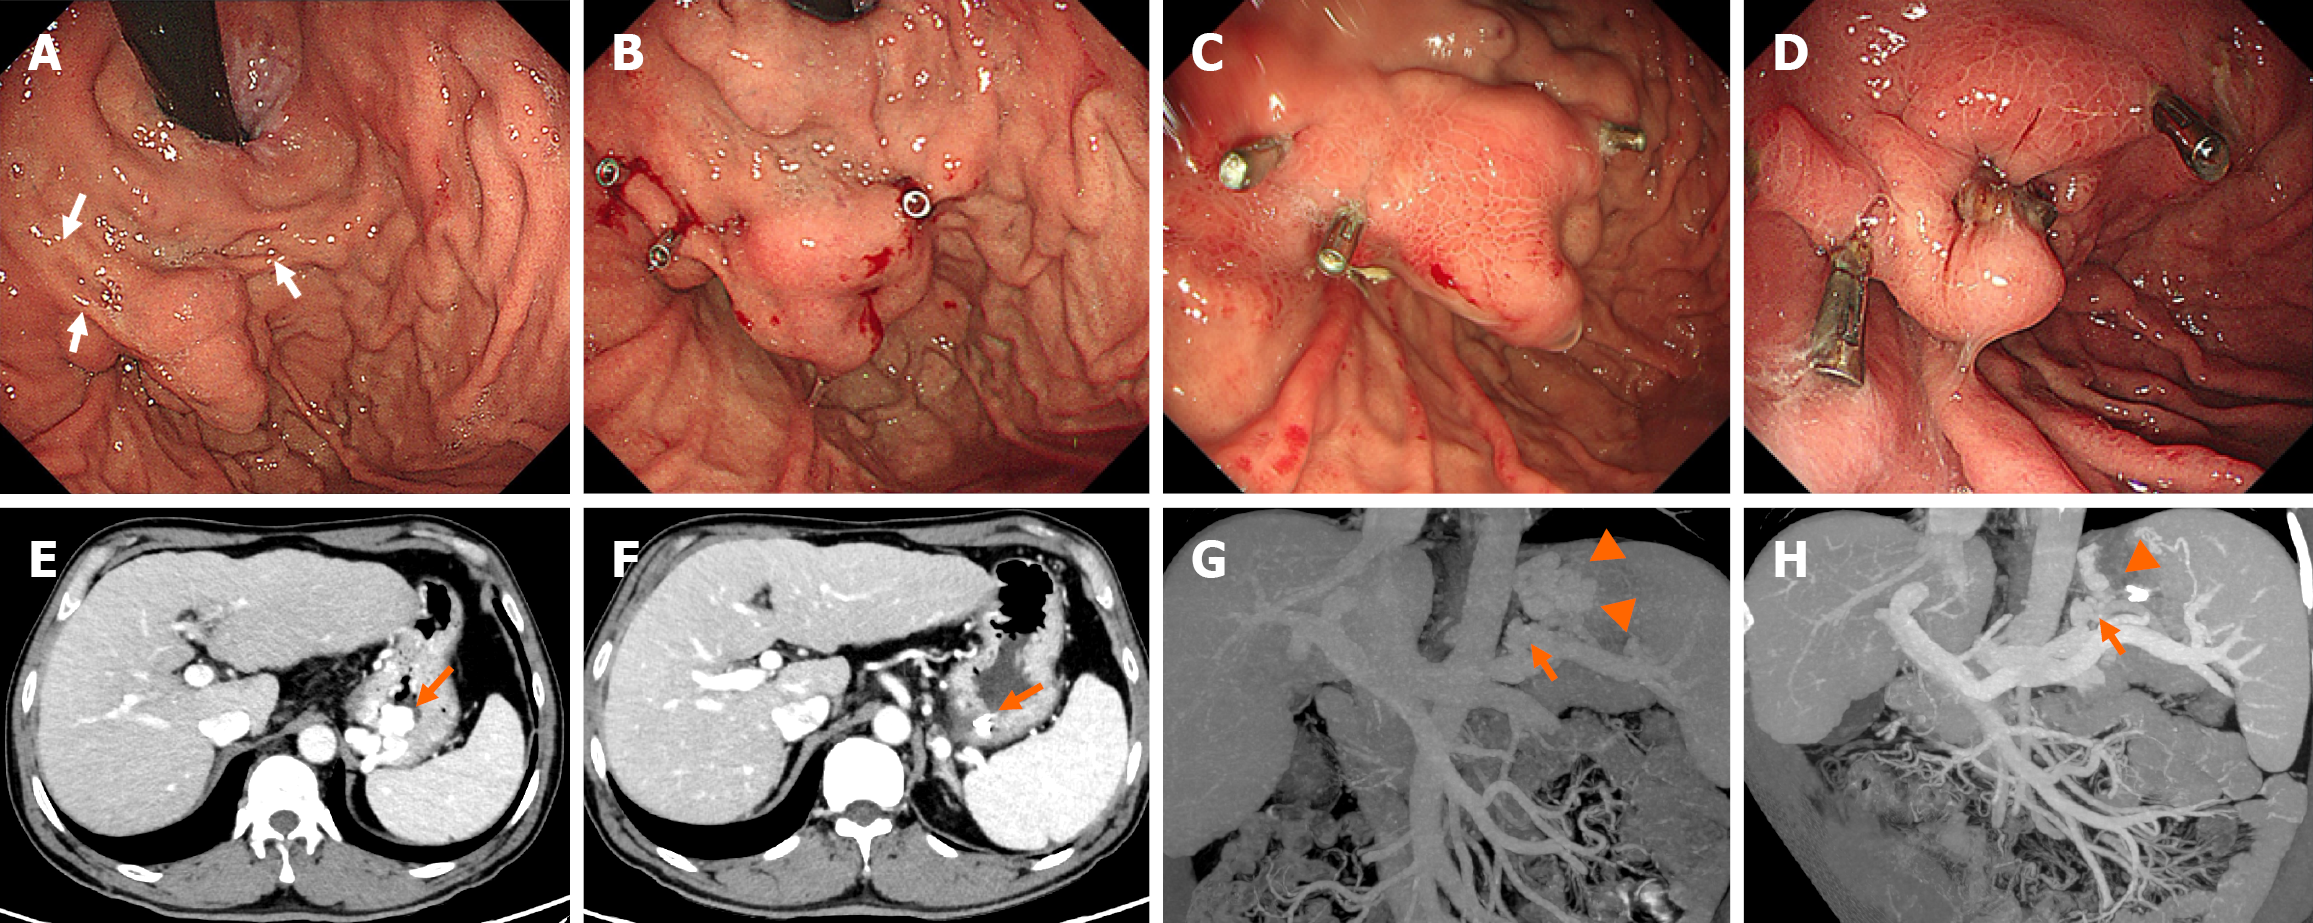

Figure 2 A 48-year-old man with tortuous gastric varices who underwent clip-assisted endoscopic cyanoacrylate injection.

A: Endoscopic examination revealed nodular gastric varices (GVs). Clips were planned to be deployed at three points (white arrows); B: Three clips were deployed on the GVs, resulting in slowing down or completely blocking the GV blood flow; C: Endoscopy revealed resolution of the GVs (with satisfactory hardening of the varix on the palpation) 30 days after the procedure; D: Endoscopy revealed postinjection ulcers 5 months after the procedure; E: Contrast-enhanced computed tomography (CT) scan showing GVs (orange arrow); F: Contrast-enhanced CT review revealed that the GVs had disappeared; the metal clips (orange arrow) could still be seen 1 week later; G: CT angiography revealed GVs (orange arrowhead) and a gastrorenal shunt (orange arrow) before the procedure; H: CT angiography revealed that the GVs had disappeared (orange arrowhead); the gastrorenal shunt was still present (orange arrow).